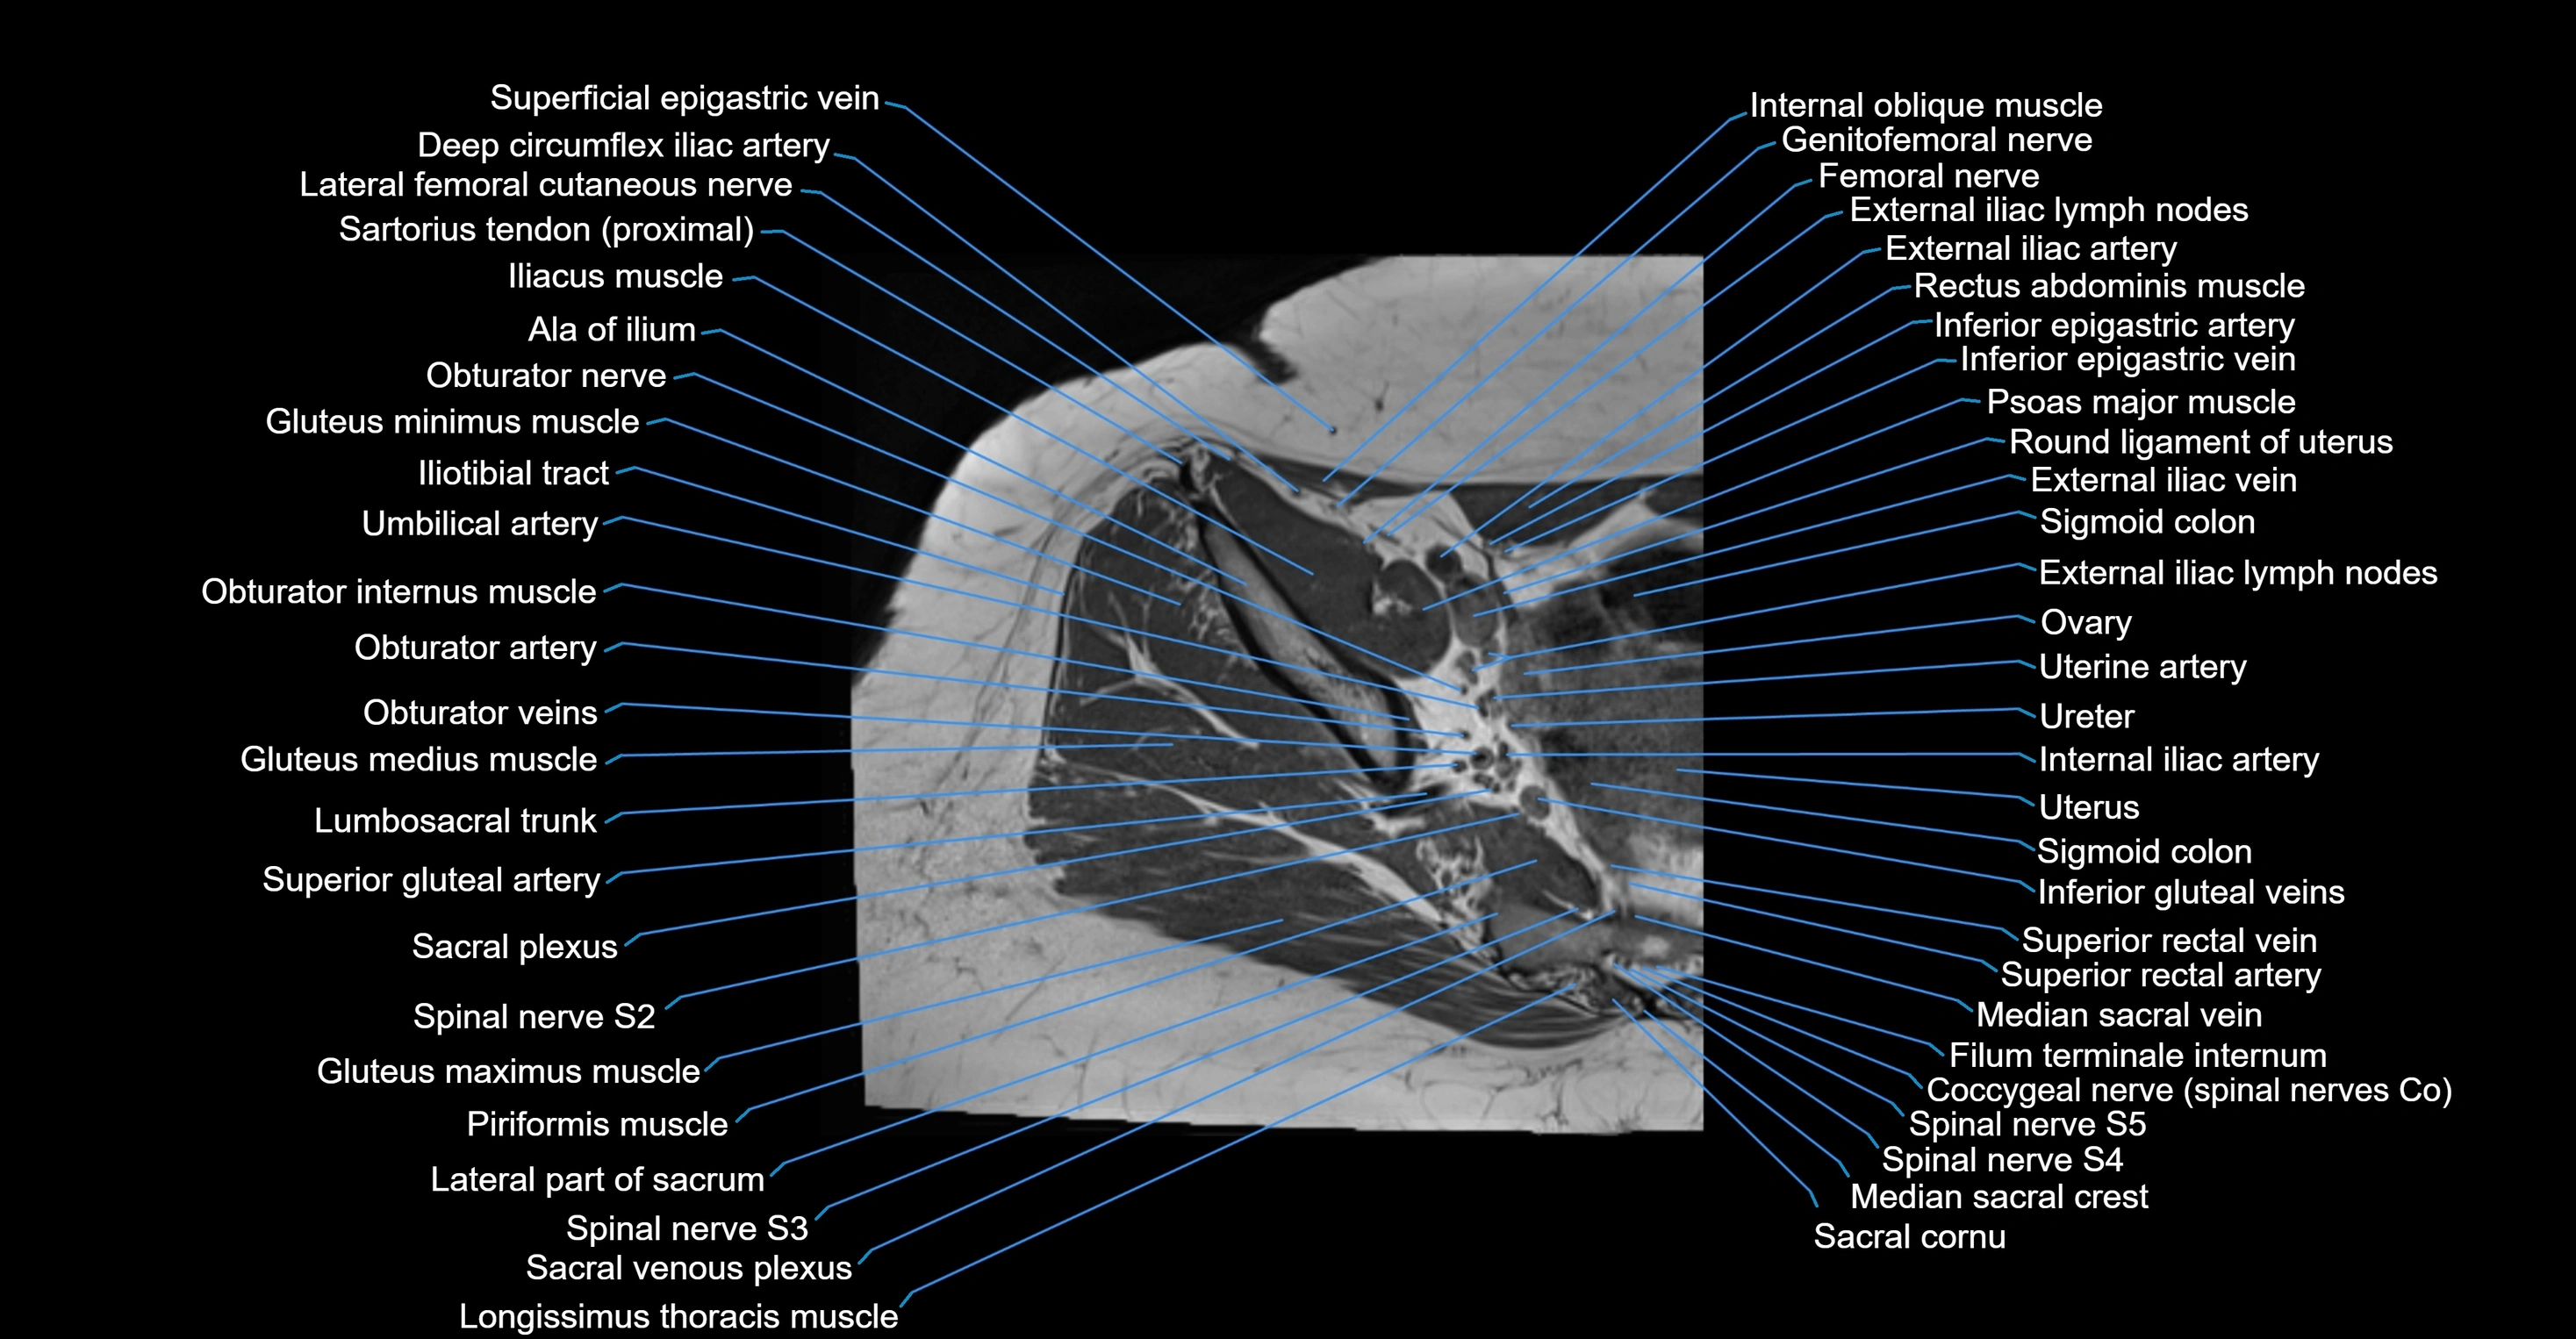

- Deep circumflex iliac artery

- External iliac artery

- External iliac lymph nodes

- External iliac vein

- Femoral nerve

- Filum terminale internum

- Genitofemoral nerve

- Gluteus medius muscle

- Gluteus minimus muscle

- Iliotibial tract

- Inferior epigastric artery

- Inferior epigastric veins

- Internal iliac artery

- Lateral femoral cutaneous nerve

- Lateral part of sacrum

- Lumbosacral trunk

- Median sacral crest

- Median sacral vein

- Obturator internus muscle

- Obturator veins

- Psoas major muscle

- Round ligament of uterus

- Sacral plexus

- Sacroiliac joint

- Sigmoid colon

- Spinal nerve S2

- Spinal nerve S3

- Spinal nerve S4

- Spinal nerve S5

- Superior gluteal artery

- Superior rectal vein

- Umbilical artery

- Uterine artery

- Uterus